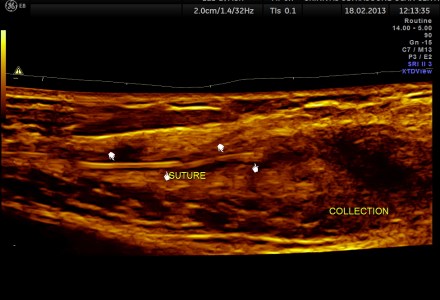

A BAD ACCIDENT

Surgeon’s nightmare